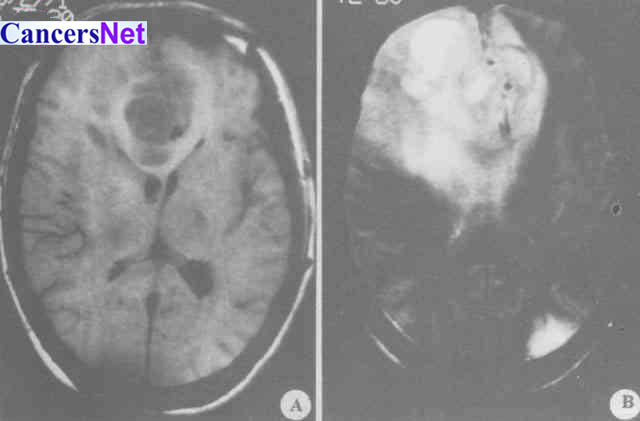

胶质母细胞瘤(图1)

胶质母细胞瘤